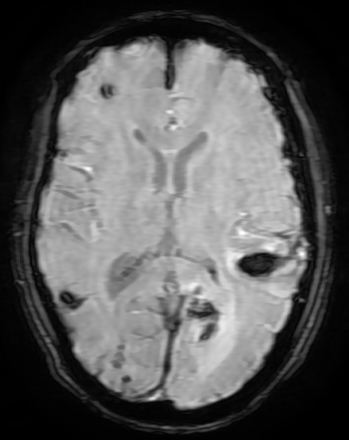

MRI Brain with cerebral angiogram revealed multi focal non-enhancing acute parenchymal hematoma - larger in left parietal and occipital lobe. Thin acute to sub-acute sub dural bleed on the left side with mild patchy diffuse gyral swelling was reported (Figure 1).

Figure 1: SW MR Image Showing Multiple Acute Haemorrhages